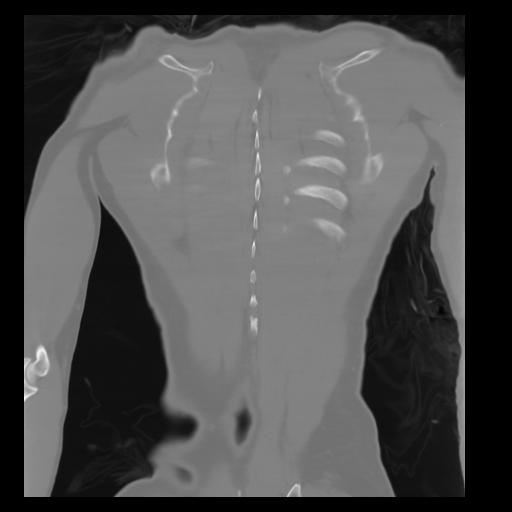

29 CUERPO,CE,Coronal,3.000,CUERPO,Coronal,